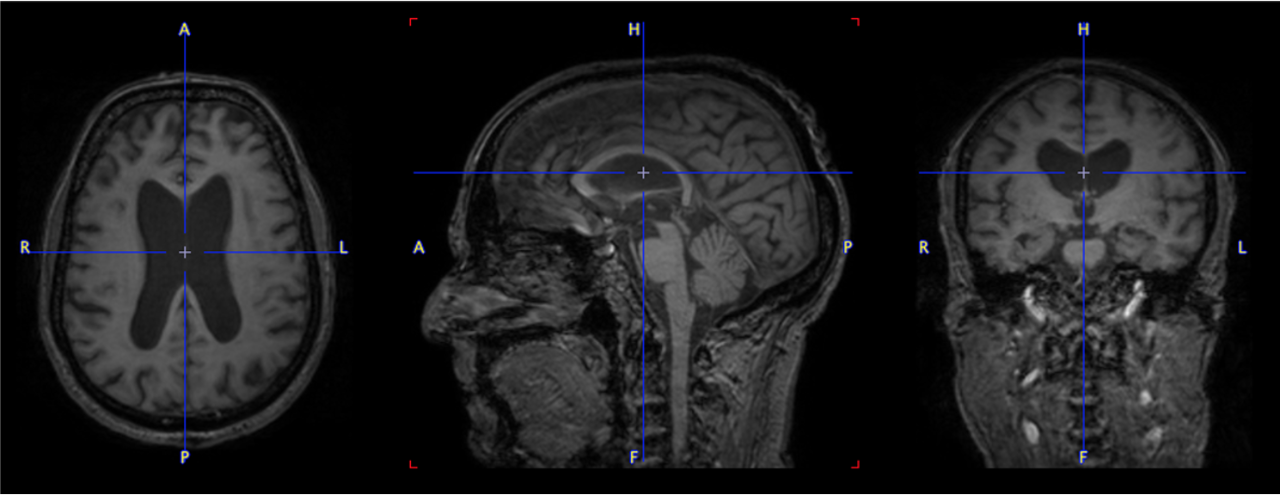

pmod’s tools provide comprehensive workflows for post-processing and quantification of imaging data for fundamental oncology research, development of radiotracers and theranostics, and in clinical research studies. Imaging scientists can trust pmod to reproducibly read their data, interpret the meta-data/units and help users calculate statistics such as SUV for their studies and publications.

• Multimodality segmentation tools – comprehensive semi-automated and manual tools for precision and reproducibility

• Full access to metadata – ensure accurate calculation of Standard Uptake Value and other key statistics

• Flexible switching between 3D and 4D datasets – direct output of time activity curves